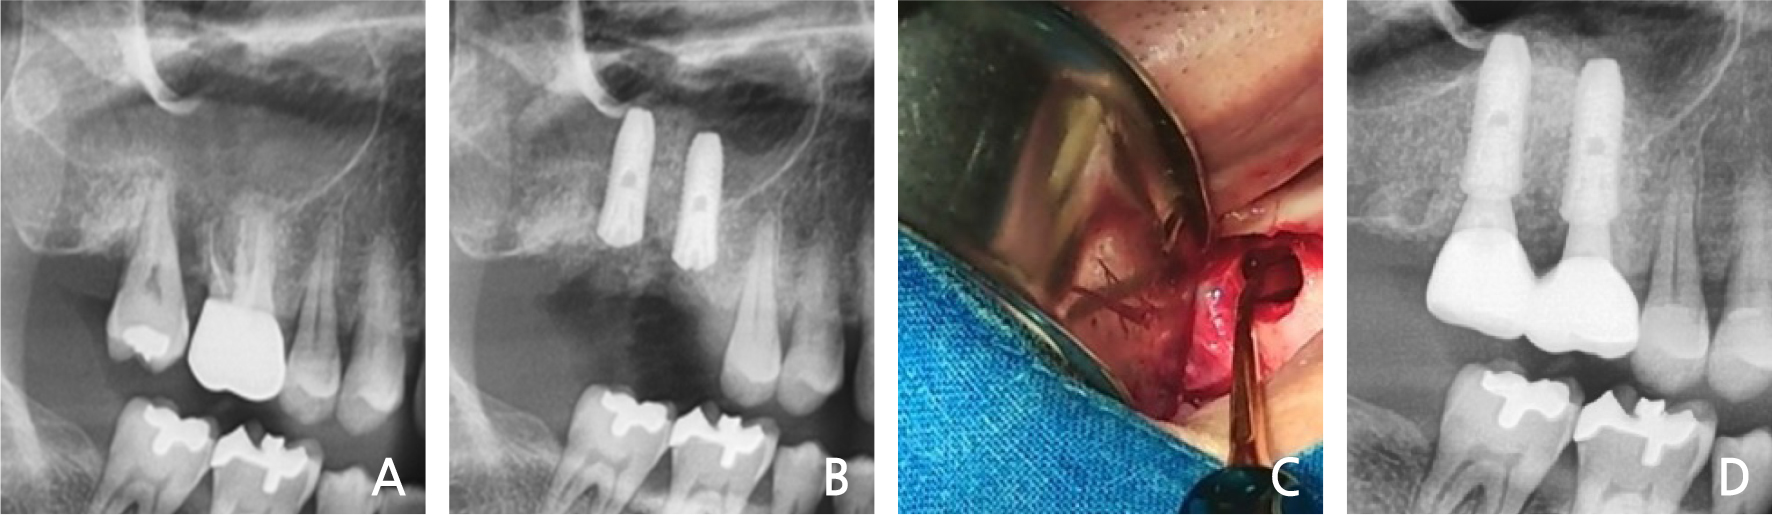

8. Case 8

A 50-year old man visited our clinic because of a fractured right maxillary 1st molar. Clinical and radiographic evaluations showed a decayed residual sinus-invading root (Fig. 8A). After extraction of the residual root, the immediate implant placement was performed with sinus elevation (Fig. 8B). During extraction, the crest area of the buccal bone plate was fractured. The fixture was placed slightly in the palatal area. Primary stability was attained from the inferior sinus wall and intact septal bone. After 3 months, loading was initiated, and a slight recession of the buccal area was observed (Fig. 8C). In radiographic view of 3-years follow-up, it was observed that the normal condition was maintained (Fig. 8D).